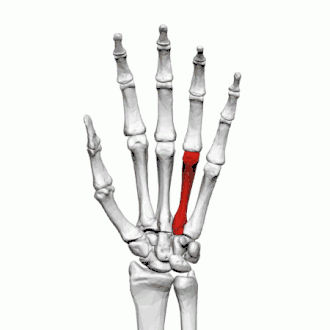

Quatrième métacarpien

Description

Le quatrième métacarpien est plus court que le troisième métacarpien.

Base

La base est petite et quadrilatère.

Sa face supérieure présente deux facettes : une grande médiale pour l'articulation avec l'hamatum, et une petite latérale pour le capitatum.

Sur le côté radial se trouvent deux facettes ovales, pour l'articulation avec le troisième métacarpien, et sur le côté ulnaire une seule facette concave, pour le cinquième métacarpien.

Corps

La diaphyse donne naissance au deuxième muscle interosseux palmaire et aux troisième et quatrième muscle interosseux dorsaux de la main.